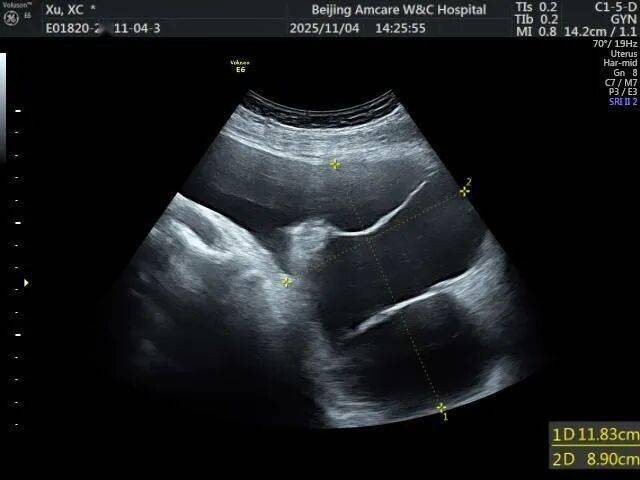

1. 超声检查:首选且最常用的检查。B超下可见盆腔内囊性无回声区,边界多不清晰,形态不规则,囊壁薄而模糊,内部无血流信号,结合患者有手术史或盆腔炎病史,可初步诊断。

2. 影像学进一步检查:若超声无法明确,可做盆腔CT或MRI。CT/MRI能更清晰地显示假囊的位置、大小、与周围器官的关系,排除恶性病变(如卵巢癌、转移性肿瘤等)。